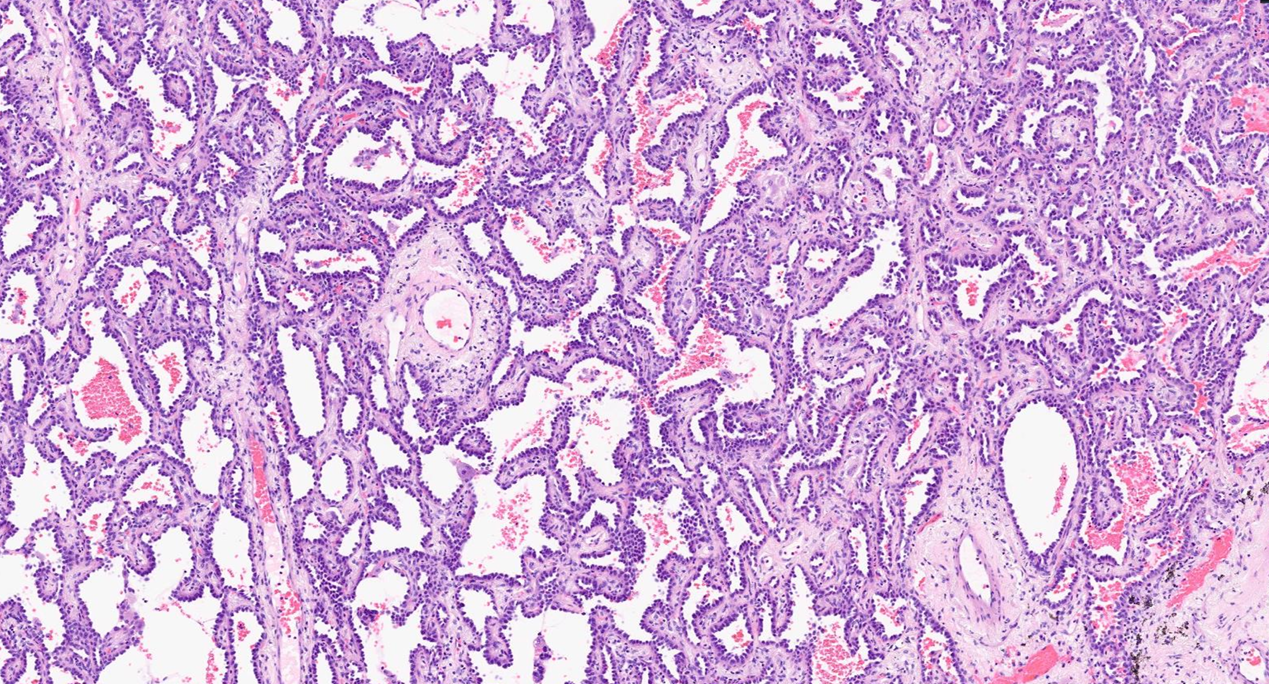

病理学报告:两个独立的腺癌

术后病理证实右中叶的两个结节均为浸润性腺癌。

组织学类型:浸润性腺癌,以贴壁型为主(70%),伴腺泡型(30%)。肿瘤总大小:17x10x5mm(pT1b)。浸润灶大小:13x7mm。组织学分级:中分化(G2)。病理特征:未见STAS,未见胸膜侵犯(PL0),淋巴血管侵犯阴性,切缘阴性。

组织学类型:浸润性腺癌,腺泡型。肿瘤总大小:5x3 mm。浸润灶大小:5x3mm。组织学分级:中分化(G2)。病理特征:未见STAS,未见胸膜侵犯(PL0),淋巴血管侵犯阴性,切缘阴性。